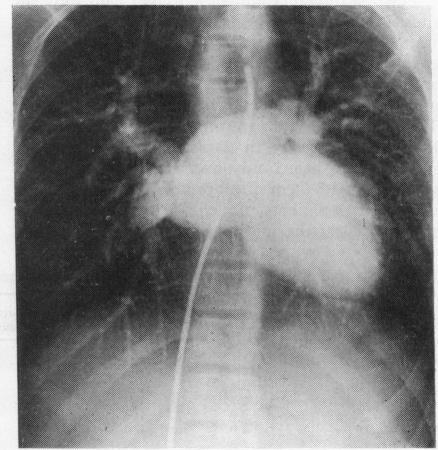

Twenty-eight cases of infradiaphragmatic total anomalous pulmonary venous return are presented, 17 without associated complex intracardiac anomalies (group A), and 11 with additional complex lesions (group B). The anomalous site of connection was to the portal vein in 19 cases (68%), to the inferior vena cava in 4 (14%), the ductus venosus in 2 (7%), to the left hepatic vein in 2 (7%), and unknown in one. A patent foramen ovale was present in 82 per cent of cases in group A and 40 per cent in group B and was frequently associated with a small left atrium and left ventricle. Nine cases (8 in group A; 1 in group B) had surgical correction, with 3 long-term survivors. The surgical mortality was 66 per cent. The postoperative haemodynamic status of the 3 surviving patients is very satisfactory, though 1 had a residual atrial septal defect. Factors which adversely affected the surgical outcome were: (1) a critically ill infant, (2) small left atrium and left ventricle, (3) a patent foramen ovale rather than atrial septal defect, (4) systemic arterial oxygen saturation less than 70 per cent, and (5) pulmonary arterial pressure in excess of systemic arterial pressure. The mortality for the entire series was 93 per cent.

本文报告了28例膈下完全性肺静脉异位引流病例,其中17例无相关复杂心内畸形(A组),11例合并其他复杂病变(B组)。异常连接部位为门静脉19例(68%),下腔静脉4例(14%),静脉导管2例(7%),左肝静脉2例(7%),1例部位不明。A组82%的病例和B组40%的病例存在卵圆孔未闭,且常伴有左心房和左心室较小。9例(A组8例;B组1例)接受了手术矫正,3例长期存活。手术死亡率为66%。3例存活患者术后血流动力学状态非常满意,尽管1例有残余房间隔缺损。对手术结果产生不利影响的因素包括:(1)危重病婴;(2)左心房和左心室较小;(3)卵圆孔未闭而非房间隔缺损;(4)体动脉血氧饱和度低于70%;(5)肺动脉压超过体动脉压。整个系列的死亡率为93%。